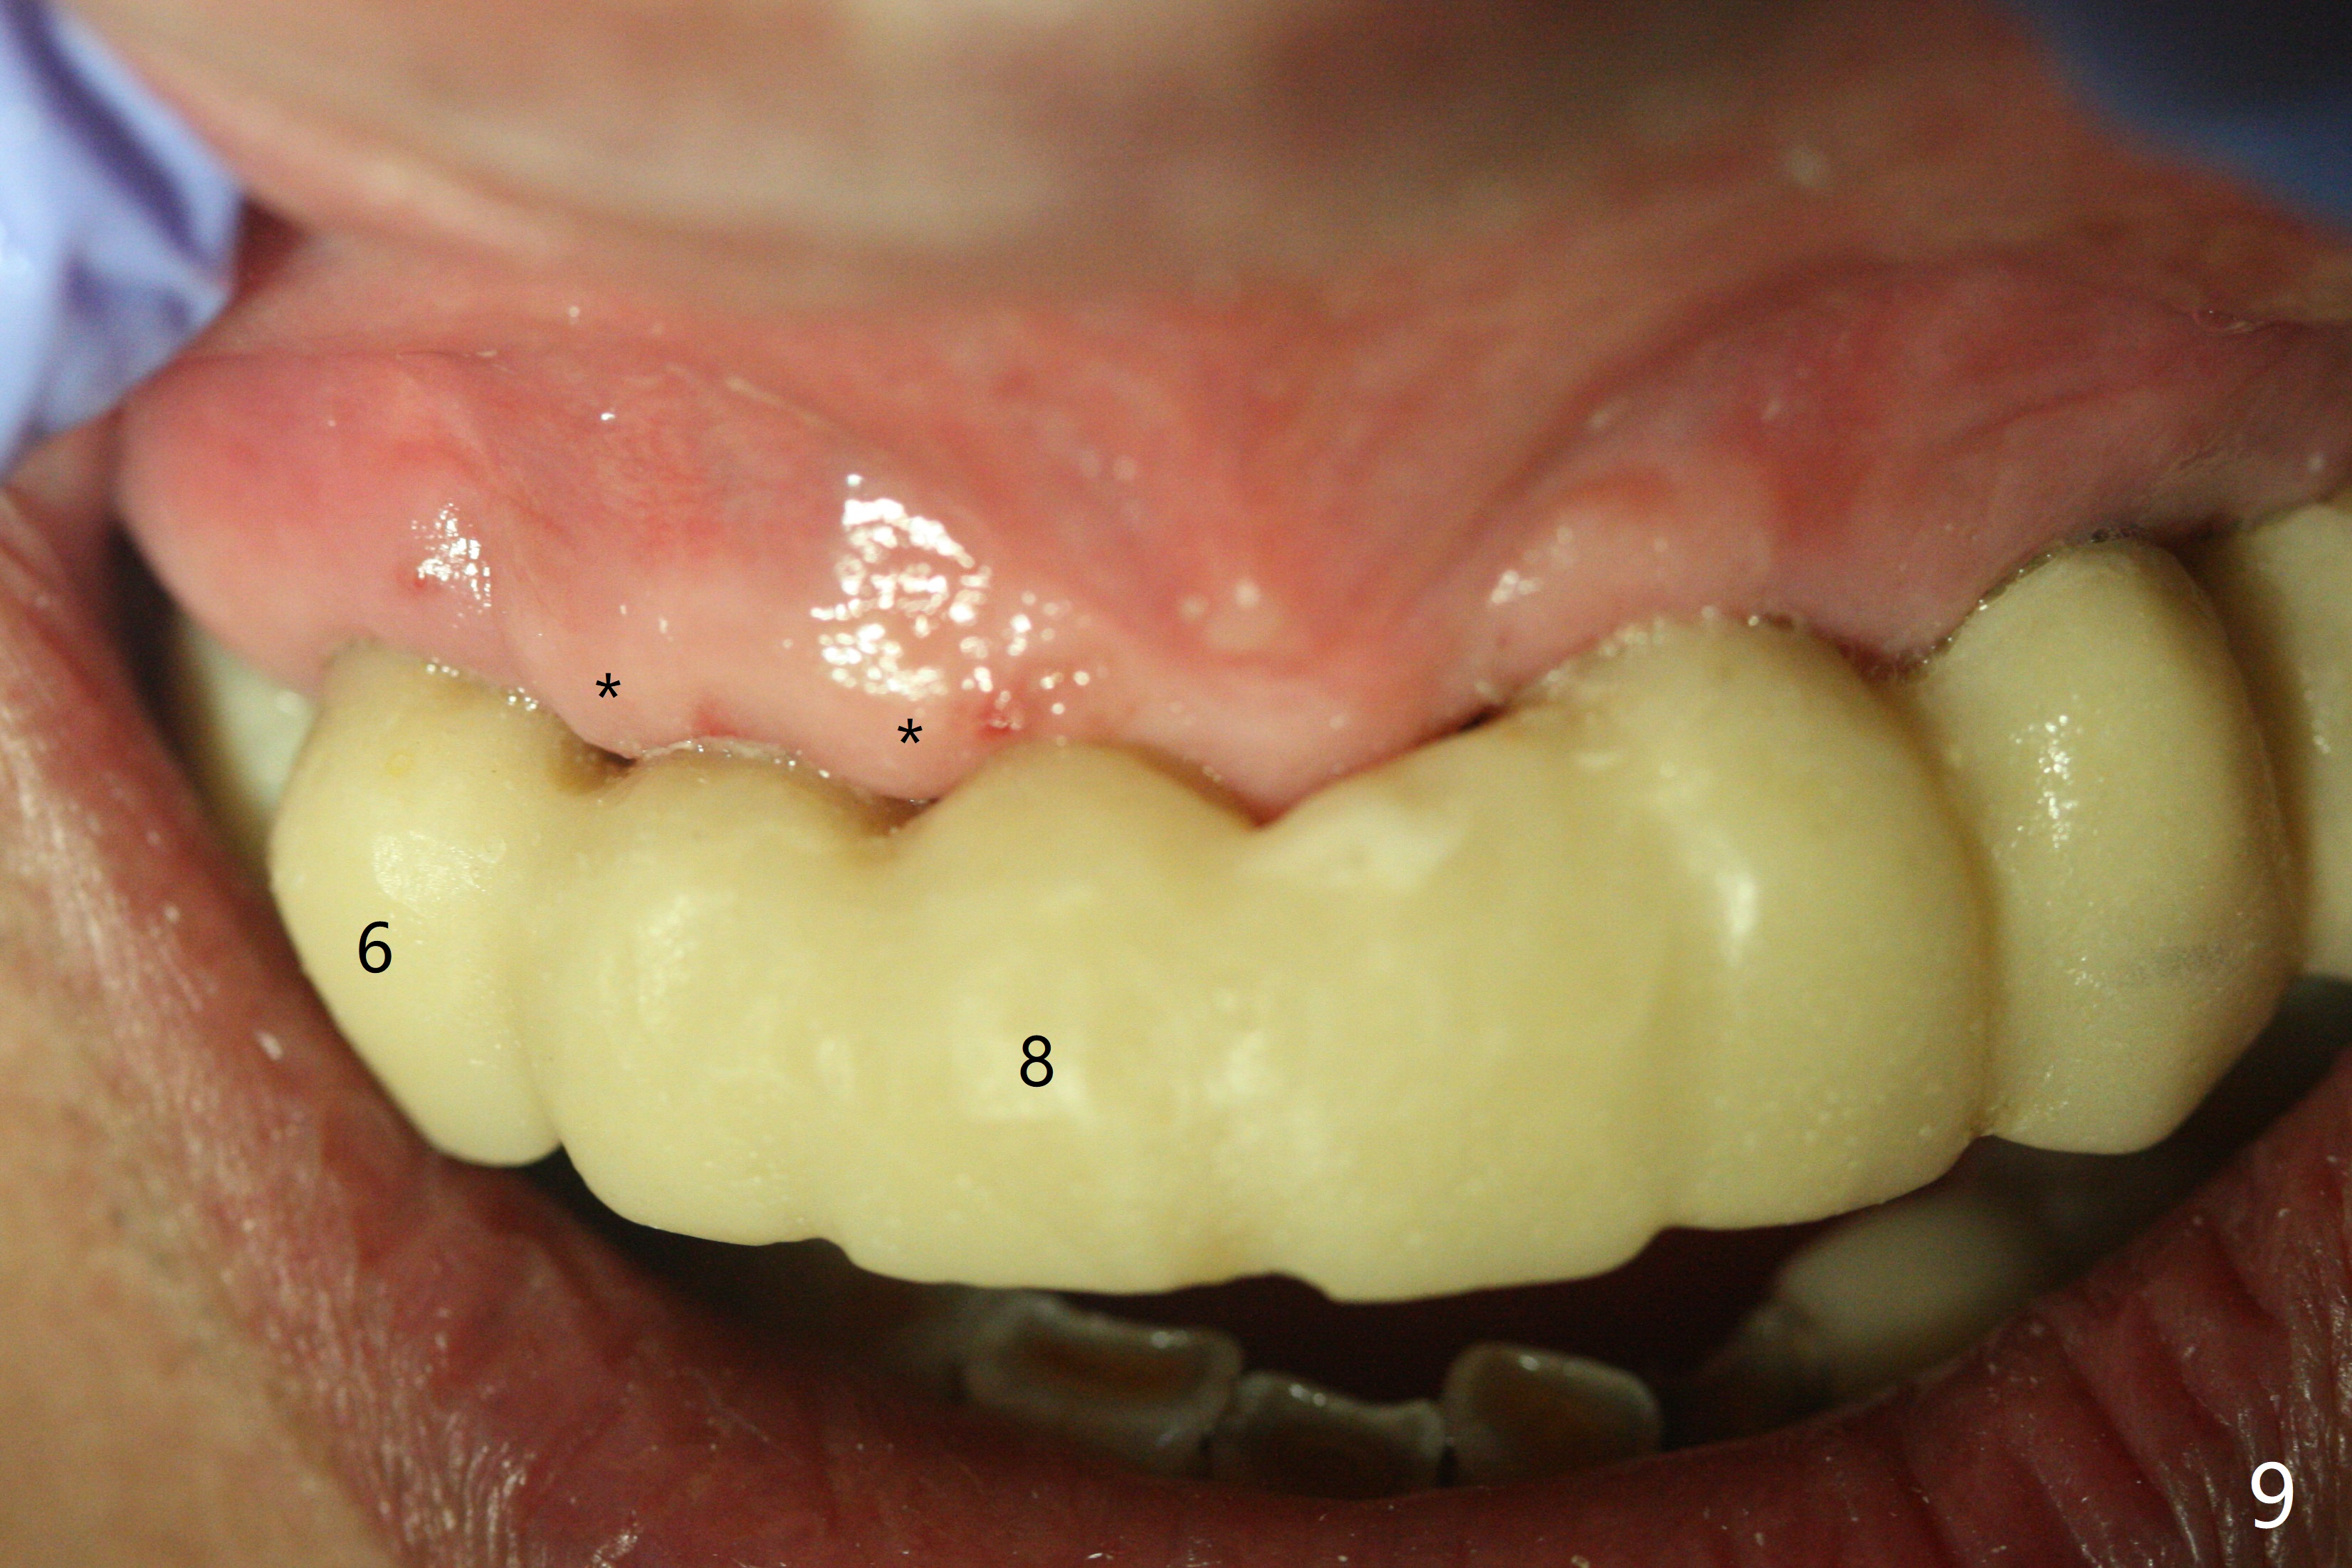

With temporarization of #3,4,13-15 (Fig.1), the anterior clearance is maintained (Fig.2). When provisional is removed, there is no papilla between #7 and 8 (Fig.3,4). After confirmation of complete seating of the abutments at #6 and 10 (Fig.5,6), gingivectomy is conducted with Diode laser (Fig.7,8). Following provisional being relined and modified, the anterior papillae form (Fig.9).